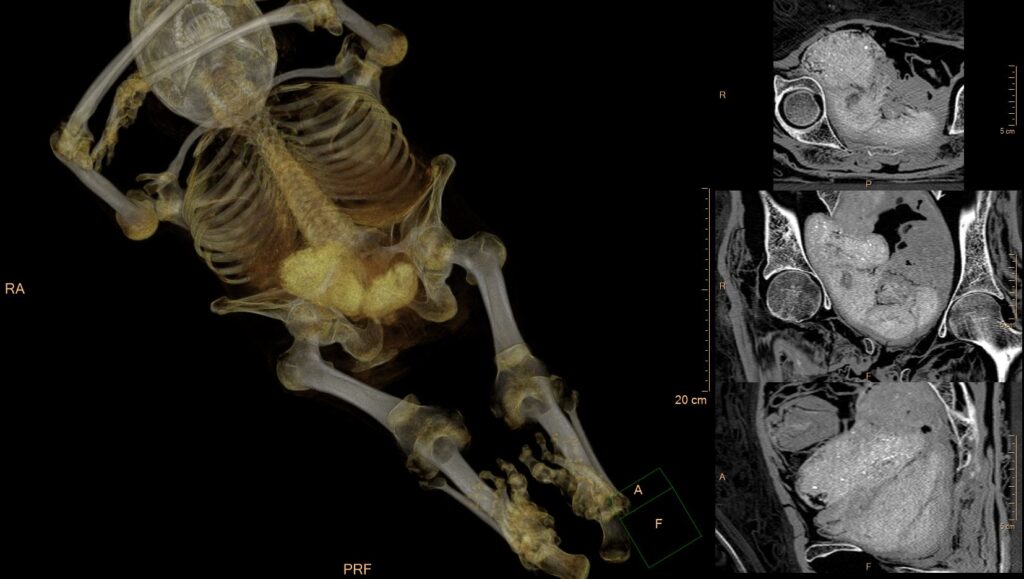

A set of objects in the the mummy’s pelvis, interpreted as the alleged fetus. A 3D reconstruction of the entire and reconstructed 2D cross-sections through the pelvis packages. CT scan and postprocessing: Ł. Kownacki